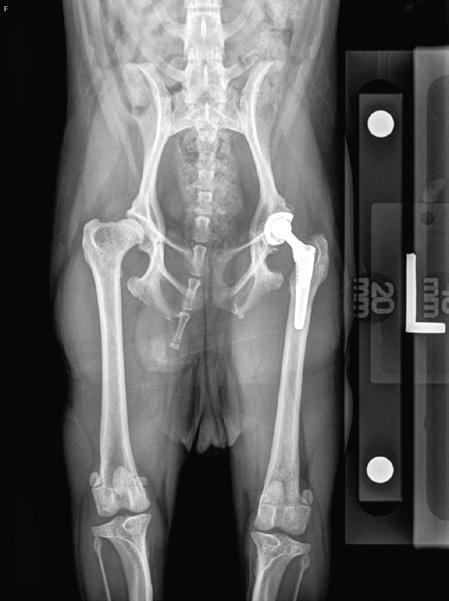

Total hip replacement is heralded as the gold standard for hip dysplasia treatment. During this procedure, the entire hip joint is replaced with a stainless steel or titanium stem and a polyethylene cup, using either bone cement or pressfit with bone ingrowth.

Total hip replacement is particularly well-suited for medium and large dogs with significant hip joint changes and even those with 0-10% femoral head coverage. The advantage of a total hip replacement, it can be done in any size dog at at any age, once the dog is skeletally mature.

Hip dysplasia is one of the most common skeletal disorders and causes of lameness in dogs. Many companion animals suffer from debilitating hip dysplasia, leading to hip subluxation with secondary osteoarthritis (see figure 1 and photo- pre and post-operative 2-year-old 2.8kg Brussels). Other causes of hip pain may be secondary to traumatic round ligament tear, hip luxation, osteonecrosis, or femoral head or neck fracture. Avascular necrosis of the femoral head and neck (Legg-Calve-Perthes disease) and slipped femoral capital epiphysis (SFCE) are conditions more prominent in small breed dogs and cats. Maine Coons and male, neutered cats have an increased predisposition for SFCE, with up to 36-41% of affected cats having bilateral disease.¹,²

Most hip replacement patients bear weight on the surgical limb immediately after surgery, in contrast to FHO, which requires physical rehabilitation to regain limb use and range of motion. THR patients have immediate normal joint biomechanics and often feel “too good, too soon” during the early osteointegration period, requiring strict owner compliance with leash restriction and avoidance of slick floors.

The goal of this article is to increase awareness in our veterinary population and general public about the availability and excellent outcomes with total hip replacement, not only in our large breed canine patients but also in small breeds and cats as well as juvenile patients. A recent cost-effectiveness article noted that the total lifetime cost of medical management exceeded that of total hip replacement as long as THR was performed before 4 years of age.³ While THR may involve a more complex surgical procedure and higher initial cost compared to FHO, its potential benefits in terms of long-term joint function, pain relief, and quality of life make it a preferred option for many veterinary patients.

Early referral for total hip replacement is encouraged due to the progression of osteoarthritis, periarticular muscle mass loss, and subluxation leading to dorsal acetabular rim wear, saucerization, and bony remodeling of the proximal femur that can create surgical challenges. THR can be performed close to skeletal maturity, and in severe cases with marked subluxation, may be performed as early as 6-10 months of age.⁷ With the development of press-fit, osteo-integrated components, implants are designed to last the lifetime of the pet.